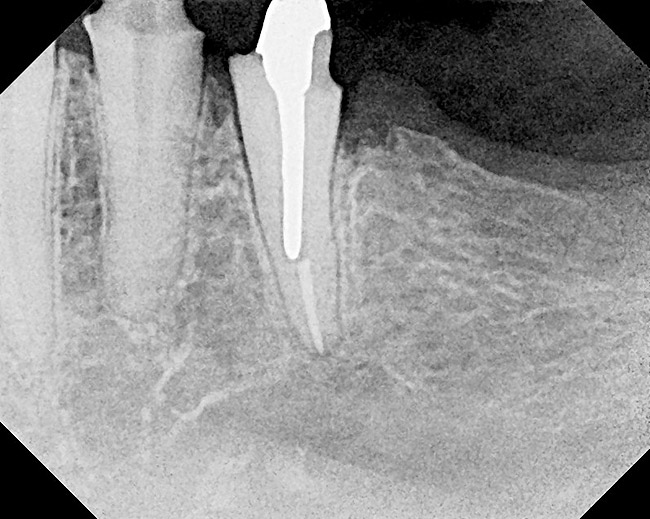

Figure 22  Radiograph taken 8 weeks after closed-flap resective surgery was performed. Note that the bony contour was good, but some minor unevenness was apparent.

Figure 22

Figure 23  Radiograph taken 6 months after resective surgery and placement of the definitive prosthesis. Note how the bony crest remodeled and was much smoother than seen in the 8-week postoperative radiograph. By making the surgical correction using the closed-flap technique at the time of preparation and impression taking, a significant amount of operative time (> 6 months) was saved and an excellent biologic result was achieved.

Figure 23